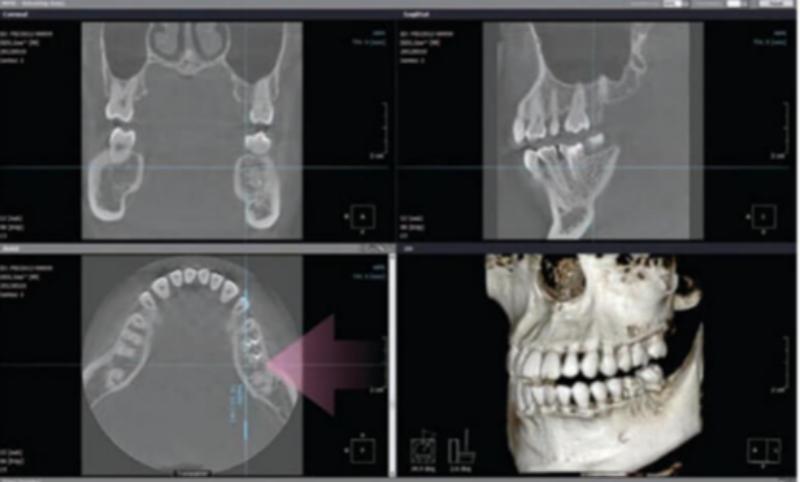

セレックシステムも導入されており最短1日でセラミックの詰め物や被せ物を終えられる(※治療前の検査・治療後の経過観察が必要になる場合があります)そうで、クラスB減菌器や口腔外バキューム、メディカルライトエアー、歯科用CTなど

インプラント治療に力を入れた診療を行われています。クリニックには専門の歯科医師が在籍しており、歯科用CTなどの専門機器も完備。駅近な好立地で駐車場も備えているため、快適な通院環境で質の高い治療を受けることができます。